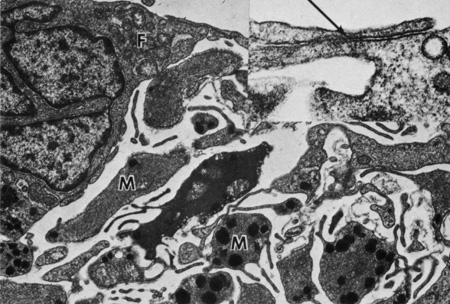

Iris vessels include arterioles, venules, and capillaries. Prior authors have described the light-microscopic morphology of iris blood vessels as “a tube within a tube.”29 It is believed that this angioarchitecture helps to prevent luminal occlusion from folds or kinks created by iris dilation. Iris arterioles are lined with endothelium and surrounded by pericytes (Fig. 16). A longitudinally oriented layer of smooth muscle may be external to the arteriole. External to the muscle is a light collagenous zone, which is in turn surrounded by an outer, dense, collagenous zone. Melanocytes and fibroblasts are found in the adjacent stroma. Iris venules have very thin walls consisting of endothelium surrounded by a thin layer of collagen. Capillaries are formed by a single layer of unfenestrated epithelium. Nerves may be present along larger blood vessels, in the anterior border layer, in the stroma, or among the muscles. Iris nerves are generally unmyelinated, although some may be enclosed by Schwann cells (Fig. 17).

Fig. 16. Upper inset shows small iris stromal arteries (arrows) (Masson trichrome, ×130). Scanning electron micrograph in lower inset shows red blood cells in the lumen of an iris stromal artery surrounded by a wide collagenous zone (×800). The transmission electron micrograph shows an endothelial (E) lining of the stromal blood vessel with adjacent basement membrane (asterisk). A pericyte is indicated by P (×6450).

Fig. 17. Myelinated nerve (N) in the iris stroma near the sphincter muscle. Smooth muscle cells are indicated by M (×18,000). Inset shows myelinated nerve with lipid material (L) (×30,000).